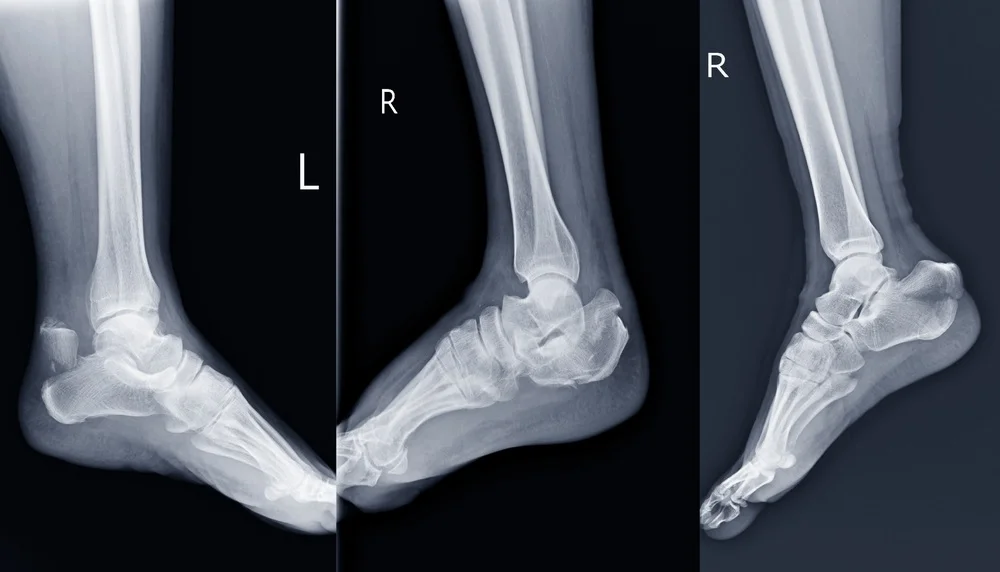

Εφόσον παρατηρηθούν κάποια από τα παραπάνω συμπτώματα, ο ασθενής πρέπει άμεσα να απευθυνθεί σε έναν εξειδικευμένο γιατρό για ποδοκνημικές κακώσεις. Άρχικα, θα ληφθεί το ιστορικό του ασθενή που περιλαμβάνει τη συμπτωματολογία και λεπτομέρειες γύρω από τον τραυματισμό και θα προχωρήσει σε κλινική εξέταση προκειμένου να ελέγξει την ευκαμψία και την κίνηση του αστραγάλου. Σε αρκετές περιπτώσεις, ζητείται από τον ασθενή μια ακτινογραφία ή μαγνητική τομογραφία προκειμένου να διερευνηθεί ενδελεχώς ο βαθμός της κάκωσης.

Από τους πιο συχνούς τραυματισμούς ανεξαρτήτως ηλικίας είναι τα κατάγματα  της ποδοκνημικής. Συγκεκριμένα, είναι η κάκωση του αστραγάλου μπορεί να  αφορά το σπάσιμο ενός οστού ή και πολλαπλών με αποτέλεσμα η άρθρωση να παρουσιάζει αστάθεια.

Τα κατάγματα ποδοκνημικής ενδέχεται να είναι:

• Έξω σφυρού, δηλαδή τραυματισμός της περόνης που βρίσκεται εξωτερικά.

• Έσω σφυρού που αφορά την κνήμη.

• Αμφισφύριο, όπου υπάρχει κάκωση έσω και έξω σφυρού.

• Τρισφύριο στην περίπτωση της κάκωσης έσω, έξω και οπίσθιου σφυρού.